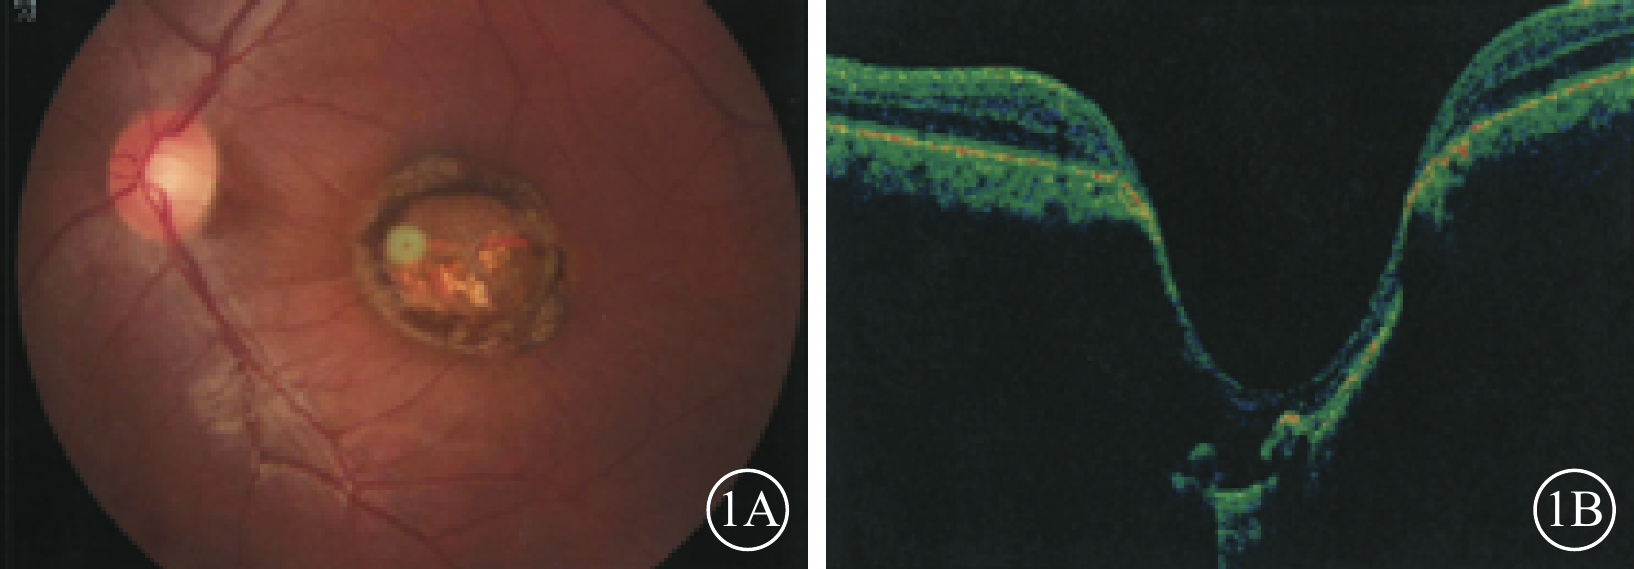

例1 患者男,24歲。因自幼雙眼視力差于2016年12月來我院眼科就診。父母非近親結婚,除其兄自幼雙眼視力差外,余家族史無特殊。否認夜盲及全身病史、母親孕期感染及藥物使用史。眼科檢查:雙眼眼位正,無眼球震顫。雙眼視力0.1,均不能矯正。右眼眼壓18 mmHg(1 mmHg=0.133 kPa),左眼眼壓19 mmHg。雙眼瞳孔對光反射遲鈍,其余眼前節檢查正常。右眼視盤邊界清楚,顏色基本正常,杯盤比(C/D)=0.3;視網膜平復,黃斑區可見約1/5個視盤直徑(DD)大小的橫橢圓形缺損區,其邊界清晰,中間透見脈絡膜血管。左眼視盤邊界清楚,顏色淡黃,C/D=0.3;視網膜平復,黃斑區可見約1.5 DD大小的類圓形缺損區(圖1A);其邊界清晰,凹陷深,中間可見灰白色鞏膜組織,透見脈絡膜大血管,病變邊緣可見色素沉著。光相干斷層掃描(OCT)檢查,右眼黃斑缺損區視網膜外層結構缺失,橢圓體帶缺損,視網膜色素上皮(RPE)層完整;左眼黃斑缺損區視網膜脈絡膜組織隨鞏膜組織局限性向外凹陷,凹陷區域內視網膜神經上皮層明顯變薄,部分缺損,其下方可見淺脫離(圖1B)。基因檢查:患者攜帶下列雜合突變:(1)RP9 c. 448C>T,p. R150*;(2)VSX1 c. 479G>T,p. G160V;(3)CEP290 c. 3573+3A>G;(4)CEP290 c. 366A>G,p. K122K。診斷:雙眼先天性黃斑缺損(色素型)。

圖1

例1患者左眼彩色眼底、OCT像。1A. 彩色眼底像,黃斑區可見一大小約1.5 DD的類圓形缺損區,邊界清晰,病灶邊緣存在色素沉著;1B. OCT像,黃斑缺損區視網膜脈絡膜組織局限性向外凹陷,凹陷區域內視網膜神經上皮層可見部分缺損

圖1

例1患者左眼彩色眼底、OCT像。1A. 彩色眼底像,黃斑區可見一大小約1.5 DD的類圓形缺損區,邊界清晰,病灶邊緣存在色素沉著;1B. OCT像,黃斑缺損區視網膜脈絡膜組織局限性向外凹陷,凹陷區域內視網膜神經上皮層可見部分缺損

例1 患者男,24歲。因自幼雙眼視力差于2016年12月來我院眼科就診。父母非近親結婚,除其兄自幼雙眼視力差外,余家族史無特殊。否認夜盲及全身病史、母親孕期感染及藥物使用史。眼科檢查:雙眼眼位正,無眼球震顫。雙眼視力0.1,均不能矯正。右眼眼壓18 mmHg(1 mmHg=0.133 kPa),左眼眼壓19 mmHg。雙眼瞳孔對光反射遲鈍,其余眼前節檢查正常。右眼視盤邊界清楚,顏色基本正常,杯盤比(C/D)=0.3;視網膜平復,黃斑區可見約1/5個視盤直徑(DD)大小的橫橢圓形缺損區,其邊界清晰,中間透見脈絡膜血管。左眼視盤邊界清楚,顏色淡黃,C/D=0.3;視網膜平復,黃斑區可見約1.5 DD大小的類圓形缺損區(圖1A);其邊界清晰,凹陷深,中間可見灰白色鞏膜組織,透見脈絡膜大血管,病變邊緣可見色素沉著。光相干斷層掃描(OCT)檢查,右眼黃斑缺損區視網膜外層結構缺失,橢圓體帶缺損,視網膜色素上皮(RPE)層完整;左眼黃斑缺損區視網膜脈絡膜組織隨鞏膜組織局限性向外凹陷,凹陷區域內視網膜神經上皮層明顯變薄,部分缺損,其下方可見淺脫離(圖1B)。基因檢查:患者攜帶下列雜合突變:(1)RP9 c. 448C>T,p. R150*;(2)VSX1 c. 479G>T,p. G160V;(3)CEP290 c. 3573+3A>G;(4)CEP290 c. 366A>G,p. K122K。診斷:雙眼先天性黃斑缺損(色素型)。

圖1

例1患者左眼彩色眼底、OCT像。1A. 彩色眼底像,黃斑區可見一大小約1.5 DD的類圓形缺損區,邊界清晰,病灶邊緣存在色素沉著;1B. OCT像,黃斑缺損區視網膜脈絡膜組織局限性向外凹陷,凹陷區域內視網膜神經上皮層可見部分缺損

圖1

例1患者左眼彩色眼底、OCT像。1A. 彩色眼底像,黃斑區可見一大小約1.5 DD的類圓形缺損區,邊界清晰,病灶邊緣存在色素沉著;1B. OCT像,黃斑缺損區視網膜脈絡膜組織局限性向外凹陷,凹陷區域內視網膜神經上皮層可見部分缺損